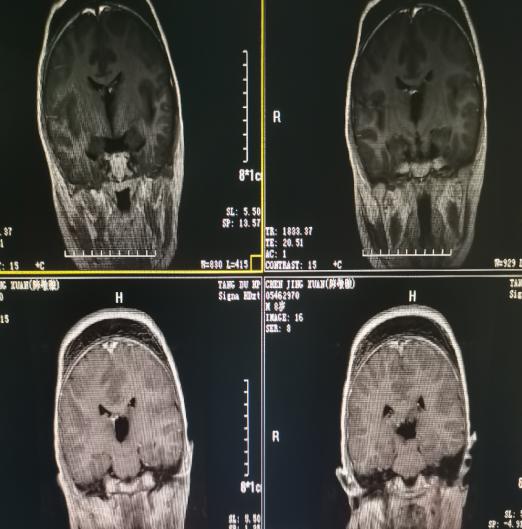

术后影像学资料: